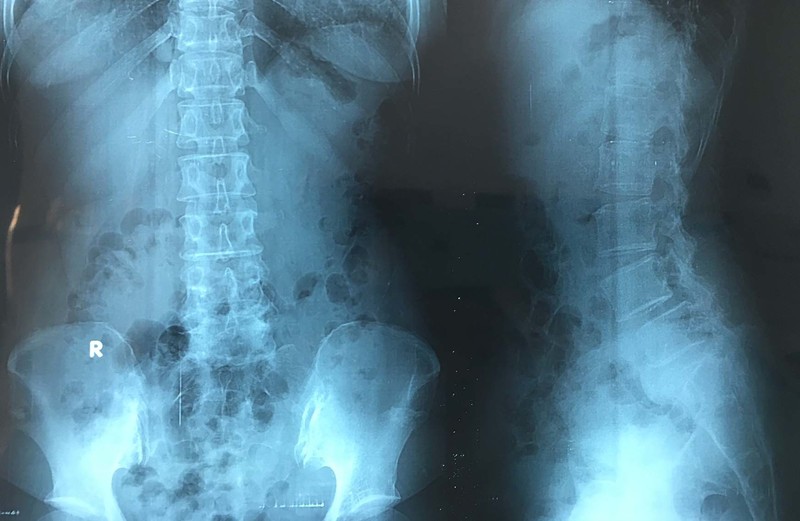

- Chụp X-quang: Chụp X-quang có thể giúp bác sĩ nhìn thấy các bất thường ở cột sống.